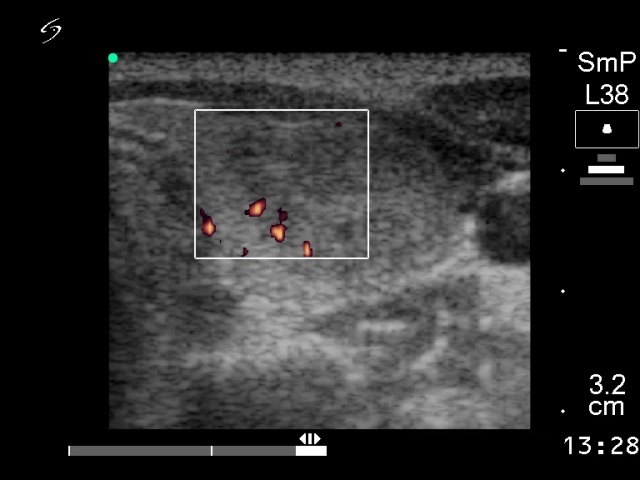

Ethanol sclerotherapy: non-toxic solid nodules - Case 5

First session of therapy (ultrasonographic picture 3)

Left lobe, horizontal scan, power Doppler mode. The lesion presents signs of intranodular blood flow.